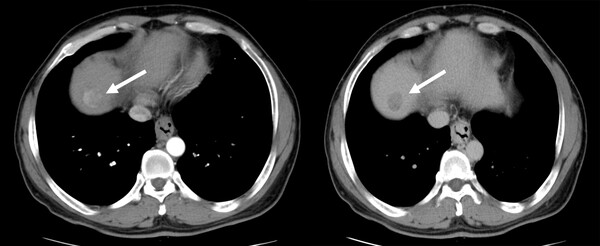

예를 들어 만성 B형 간염에 인한 간경변증 등의 위험인자가 있는 사람이 복부 초음파 검사나 종양표지자인 알파태아단백검사에서 간암으로 의심되면 CT나 MRI 검사를 시행한다. CT나 MRI 검사에서 간암을 시사하는 소견은 동맥이 보이는 시기에 조영증강 되어 하얗게 보이고 이후에 낮은 조영을 보이는 것이다. 간암은 조영증강이 잘 되는 특징을 보이는 종양인데 그 이유는 종양내에 혈관이 많기 때문이다.

간암 진단을 위한 영상검사인 CT나 MRI를 할 때 정맥을 통해 조영제라는 약을 주입하면서 검사한다. 조영제는 혈관을 일시적으로 염색하기 위한 약으로 혈관이 많은 조직에 더 많이 분포하는 특성이 있는데 이를 이용해 병변을 진단한다. 혈관이 많은 간암에는 주변 간에 비해 조영제가 더 많이 머무르게 되므로 하얗게 보이는데 이를 조영증강 된다고 한다. 조영제를 사용하지 않으면 간과 간암으로 가는 혈류에 대한 정보가 없으므로 영상검사를 통해 정확히 진단하기 어렵다. 그러나 감시검사를 초음파 대신 MRI로 하는 경우에는 조영제 없이 검사하는 경우도 있다.